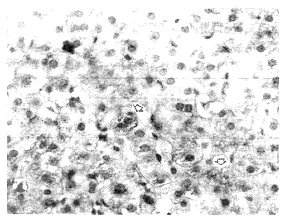

图1 庚肝患者肝穿组织切片,经特异McAb染色,阳性肝细胞胞浆呈棕黄颗粒状,相邻肝细胞染色阴性 BA染色法×1000

为进一步排除HBV和HCV的感染,对7例庚型肝炎单独感染者肝活检标本,同时进行了三种免疫组化检测,结果:HBsAg和HCV均为阴性,HGV特异性McAb染色,HGV抗原阳性者5例,HGV抗原仅分布在肝细胞浆呈棕黄色颗粒,相邻肝细胞染色阴性,见图1。为进一步阐明HGV NS5区McAb的特异性,对此进行了肝脏组织的原位杂交的观察,结果HGV基因探针阳性细胞与免疫组化相仿。

图1所示1例HGV单独感染病例,男,21岁,体检发现肝功能异常,于1995年4月28日入院无输血及使用血制品史,入院时TSB 23.34μmol/L,ALT 182IU/L,AST 82IU/L,A/G 46.9/36.1,AKP 123IU/L γ-GT 34 IU/L,血清病原学检查HNA~E均为阴性,临床诊断为“急性黄疸型肝炎”,经一般护肝药物治疗,肝功能恢复正常,住院18天出院。同年10月17日因ALT复升再次入院,半月后行肝穿刺活检,组织学显示:肝细胞浊肿,可见点状坏死及灶性坏死,汇管区有轻度纤维组织增生及淋巴细胞浸润,见图2,图3。